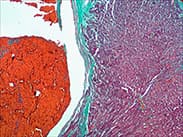

Masson氏結(jié)締組織三合染色法 |

膠原纖維 | 間胚葉來源腫瘤診斷(纖維瘤、平滑肌瘤、橫紋肌瘤、神經(jīng)纖維瘤等) | ![]() |